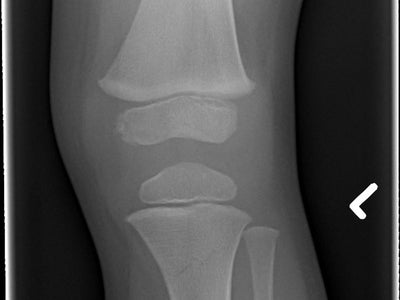

An exercise option gaining popularity is rebounding, and not with a basketball!  Rebounding is most commonly done on a mini trampoline that can be done inside or outside. It is basically jumping on a trampoline, small jumps or large jumps, exercise jumps like jumping jacks, walking or running.    The level of activity is up to you and your physical condition.  Like most exercises, you start out fairly simple and can gradually build up your length of time and type of exercises you perform on the rebounder.   There are three types of exercises you can do to get benefits from rebounding: 1.    Aerobic Bouncing Rebounding Exercise     If you're looking for a fun and energetic way to get your blood flowing, this is it! The aerobic bouncing rebounding exercise involves jumping jacks, twisted dances (think waltz), running in place or doing other moves that require high intensity.     This type of workout will make sure all parts are working hard - from heart rate up through muscles throughout our bodies; making us feel invigorated after each session because we've been able to work them out harder than ever before. 2.  The Rebounding "Health" Bounce Exercise     This exercise involves gently bouncing up and down on your trampoline without lifting the feet off of a mat. This low-impact, effective move helps increase blood flow to areas that are often missed when we're sitting too long at one time or engaged in other sedentary pursuits like watching TV, as well as activating your lymphatic system!     You can do this for longer periods while still being able interact with others around you during commercial breaks - it's almost like having another workout but indoors so no need worry about getting bored ;) 3.    The Rebounding “Strength” Bounce Exercise     This rebounder bounce involves jumping as high up in the air you can. This helps strengthen your muscles, improves balance and moves blood all over so it's good for physical fitness too!     This more difficult type of rebounding is called "strength" because this requires a lot from an individual before they will be able to complete its exercises successfully; however if within your bodies limits then give yourself permission to enjoy it!     Rebounding is unique as it uses both acceleration and deceleration to work on every cell of your body in a distinctive way.  Several actions happen as you do rebounding.  First, you accelerate as you bounce up.  Then, there is an instant of weightless pause at the top before you decelerate at an increased G-force back to the mat.  After your impact, you repeat this rebounding sequence. All you need is the mini trampoline and the space to put it. Do your research before purchasing a rebounder and make sure it is well made.        Some of the specific benefits of rebounding include: 1.    Easy on the joints.  Rebounding has much less impact on joints and soft tissues than other exercises.  2.    Anti-inflammatory effects.  Rebounding efficiently stimulates and helps lymphatic drainage which has anti-inflammatory effects on your body.  3.    Arthritis Management. This type of exercise helps lubricate the joints and reduce the pain and stiffness that comes along with this disease.   4.    Reduces the risk of falls. Rebounding helps improve balance and muscle-strengthening which can help prevent falls.  5.    Increase bone density.  Rebounding can help seniors increase their bone strength and reduce the risk of developing osteoporosis women and one in five men will break a bone because of osteoporosis.  6.    Slows muscle atrophy.  Rebounding helps slow down the inevitable muscle atrophy in the aging process.  7.    Fun and portable.  Rebounding can be done anywhere you are and it is fun.  Fun exercise means more consistent exercise and more benefits from that exercise!     HOW ELSE CAN YOU IMPROVE BONE DENSITY?      Improving your bone density is one of the best benefits of rebounding, but there are a few other good ways to help develop healthier bones.     Adding Vitamin D, Calcium and Vitamin K to your diet can help boost bone density. Not getting enough of these nutrients could decrease the strength in bones which increases risks for fractures or breaks from uneven surfaces such as stairs- especially if you have already had some prior issues with bone density!     When there isn't enough calcium around - like when we eat less dairy products due either dietary constraints (like vegetarianism) or because we're not really big fans; our bodies take what's available first then pulls the calcium directly from our bones for nourishment.      As you get older, it’s beyond important to focus on building your bone density. Using a rebounder at home is one of the easiest ways to do this! With so many rebounding benefits, it’s a no-brainer to add this powerful exercise to your routine.      As always, check with your provider before starting any new exercise program. There are also safety concerns with children and trampolines. Make sure you are in attendance should any children use your trampoline and go over the rules with them prior to use.